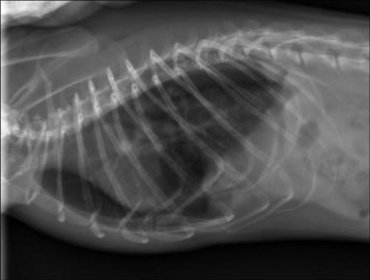

Certains d'entre vous ont vu passé en 2023 ici un sujet sur la naissance de ma 3ème portée: VIC Zelda & MAL Alpha. Et on ne vas pas se mentir, cette portée est fiasco... :( Nous avions eu 8 ratons nés le 07 mars 2023 et sur les 8, 3 déjà décédés dont 2 de soucis respiratoires. Nous avons sur cette famille commencé par Zéphyr, le frère de Zelda décédé en septembre 2023 après un long combat depuis avril. Une analyse avait été faite et révélait une bactérie ultra résistante et n'avait pas ressorti de mycoplasme. Quelques mois plus tard, Zelda a commencé à être touché par le même type de pathologie ainsi que son fils Björn. Après de longs traitements également, Zelda nous a quitté en juin et Björn en juillet alors que les traitements ne les soulageaient plus. Et a l'heure actuelle, je vois Cassian et Pénélope, toujours la même portée, développer à leur tour les mêmes symptômes. Ils sont actuellement sous traitement mais aucune analyse n'a été effectué. Je crains qu'une anesthésie lors du prélevement leur soit fatale. En revanche, des radios ont été effectués et ma vétérinaire à évoqué une fibrose pulmonaire, avec un stade plus avancé pour Cassian.

Je vous joint les radios de Cassian et Pénélope pour comparaison si vous avez également des radios de fibrose.

CASSIAN_corpsentier_face_1fibrose.jpg.9d0ebe9324977b38849b5a11505e62b9.jpgPENELOPE_corpsentier_face_1.jpg.c3f7df9c81ffd6672607b852461d1880.jpg